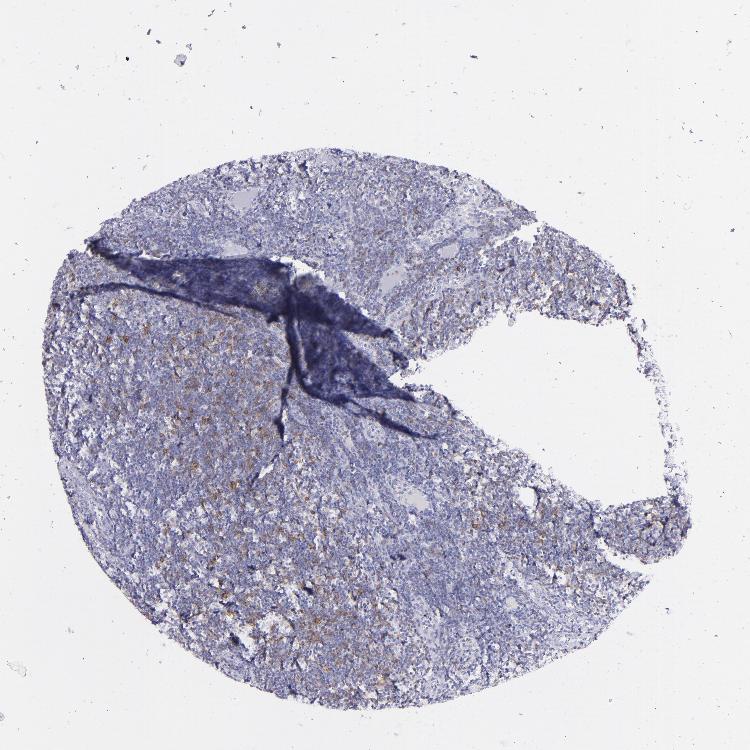

TISSUE PRIMARY DATA LYMPH NODE Show tissue menu

Lymph node

LYMPH NODE - Antibody stainingi

Antibody staining in the annotated cell types in the current human tissue is reported as not detected, low, medium, or high, based on conventional immunohistochemistry profiling in selected tissues. This score is based on the combination of the staining intensity and fraction of stained cells.

Each image is clickable and will lead to virtual microscopy that enables deeper exploration of all samples and also displays staining intensity scores, fraction scores and subcellular localization as well as patient and tissue information for each sample.

Antibody HPA050525Antibody CAB002503

Germinal center cells LowLow

Non-germinal center cells Not detectedLow